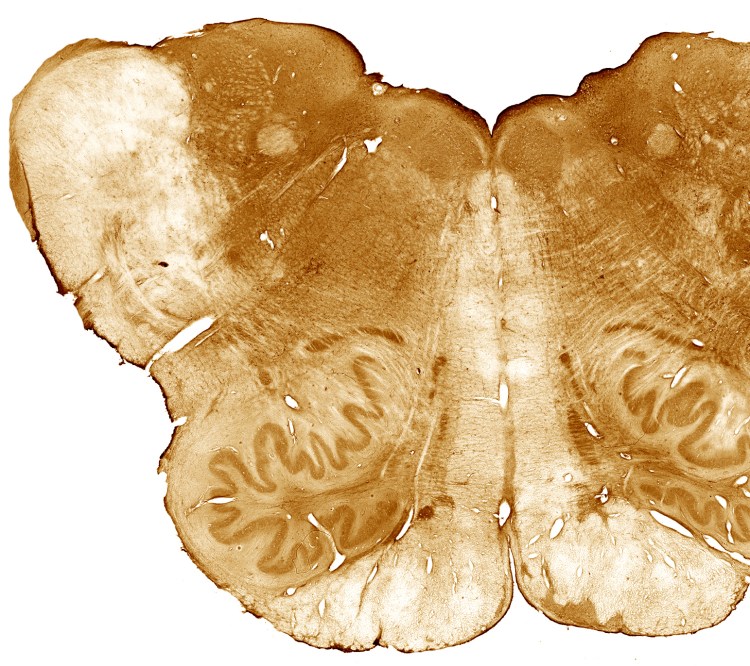

Organization and immunohistochemical properties of the human brainstem.

Organization of human brainstem nuclei.